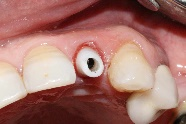

After implant placement (Figure 9), the primary stability of the implant was satisfactory (greater than 35N), the provisional abutment was fixed (Figure 10) and a post-operative retroalveolar radiograph was taken for radiological control of the implant and adaptation of the provisional abutment (Figure 11).

Figure 10. Fixing the temporary abutment to the implant